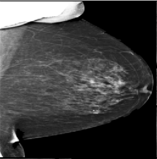

The 136 true outliers are classified into seven categories by the professional radiologist: implant, pacemaker, cardiac loop recorder, improper radiography, atypical lesion/calcification, incorrect exposure parameter and improper placement. It is worth noting that, despite the fact that mammograms with implants were eliminated during the preprocessing step (see Section 2.6), there were still mammograms with implants remaining since they were incorrectly categorised as having no implants. Figure 1 depicts representative outliers for each category, and Table. 4 displays the number and percentage of outliers in each category given that that the total number of true outliers is 136.

Figure 1: Examples of true outlier subgroups in the ADMANI dataset. From left to right and top to bottom, the outlier types are: implant, pacemaker, cardiac loop recorder, improper radiography, improper radiography, atypical lesions/calcification, incorrect exposure parameter, improper placement. Improper radiography is classified into two subtypes: those with heterogeneous pectoral muscle and the rest, respectively.